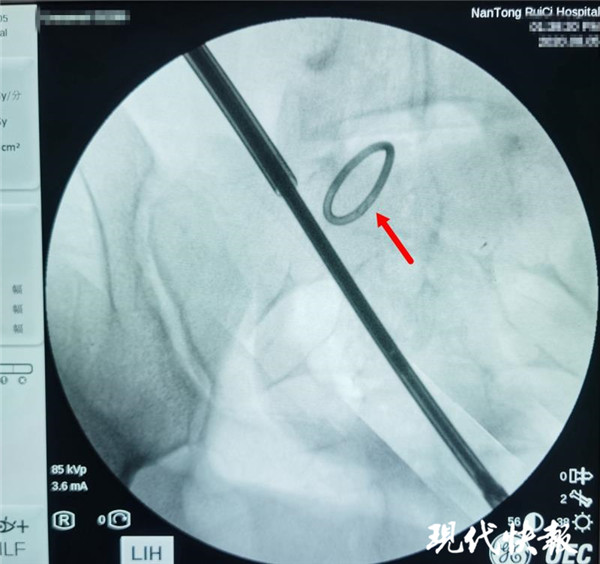

△術中X光,可清晰看到節(jié)育環(huán)

通過反復的X光定位,醫(yī)生終于發(fā)現(xiàn)了節(jié)育環(huán)的蹤跡,這枚“O”型節(jié)育環(huán)已經(jīng)跑到了乙狀結腸中段右側系膜內,并且穿透了乙狀結腸右側壁肌層,貫穿腸腔。醫(yī)生分離切開腸系膜后,看見有近一半的節(jié)育環(huán)嵌頓在腸腔內。之后胡偉和吳忠新相互配合,將節(jié)育環(huán)完整取出,并根據(jù)術中談話時患者家屬選擇的手術方案,對腸壁的兩處瘺孔進行了修補縫合,手術順利結束。